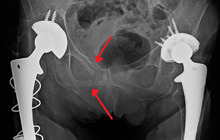

Blunt pelvic trauma

The most common causes of blunt pelvic trauma are motor vehicle accidents and multiple-story falls, and thus pelvic injuries are commonly associated with additional traumatic injuries in other locations.[28] In the pelvis specifically, the structures at risk include the pelvic bones, the proximal femur, major blood vessels such as the iliac arteries, the urinary tract, reproductive organs, and the rectum.[29][28]

.jpg)

One of the primary concerns is the risk of pelvic fracture, which itself is associated with a myriad of complications including bleeding, damage to the urethra and bladder, and nerve damage.[30] If pelvic trauma is suspected, emergency medical services personnel may place a pelvic binder on patients to stabilize the patient's pelvis and prevent further damage to these structures while patients are transported to a hospital. During the evaluation of trauma patients in an emergency department, the stability of the pelvis is typically assessed by the healthcare provider to determine whether fracture may have occurred. Providers may then decide to order imaging such as an X-ray or CT scan to detect fractures; however, if there is concern for life-threatening bleeding, patients should receive an X-ray of the pelvis.[31] Following initial treatment of the patient, fractures may need to be treated surgically if significant, while some minor fractures may heal without requiring surgery.[28]

A life-threatening concern is hemorrhage, which may result from damage to the aorta, iliac arteries or veins in the pelvis. The majority of bleeding due to pelvic trauma is due to injury to the veins.[32] Fluid (often blood) may be detected in the pelvis via ultrasound during the FAST scan that is often performed following traumatic accidents. Should a patient appear hemodynamically unstable in the absence of obvious blood on the FAST scan, there may be concern for bleeding into the retroperitoneal space, known as retroperitoneal hematoma. Stopping the bleeding may require endovascular intervention or surgery, depending on the location and severity.[29]